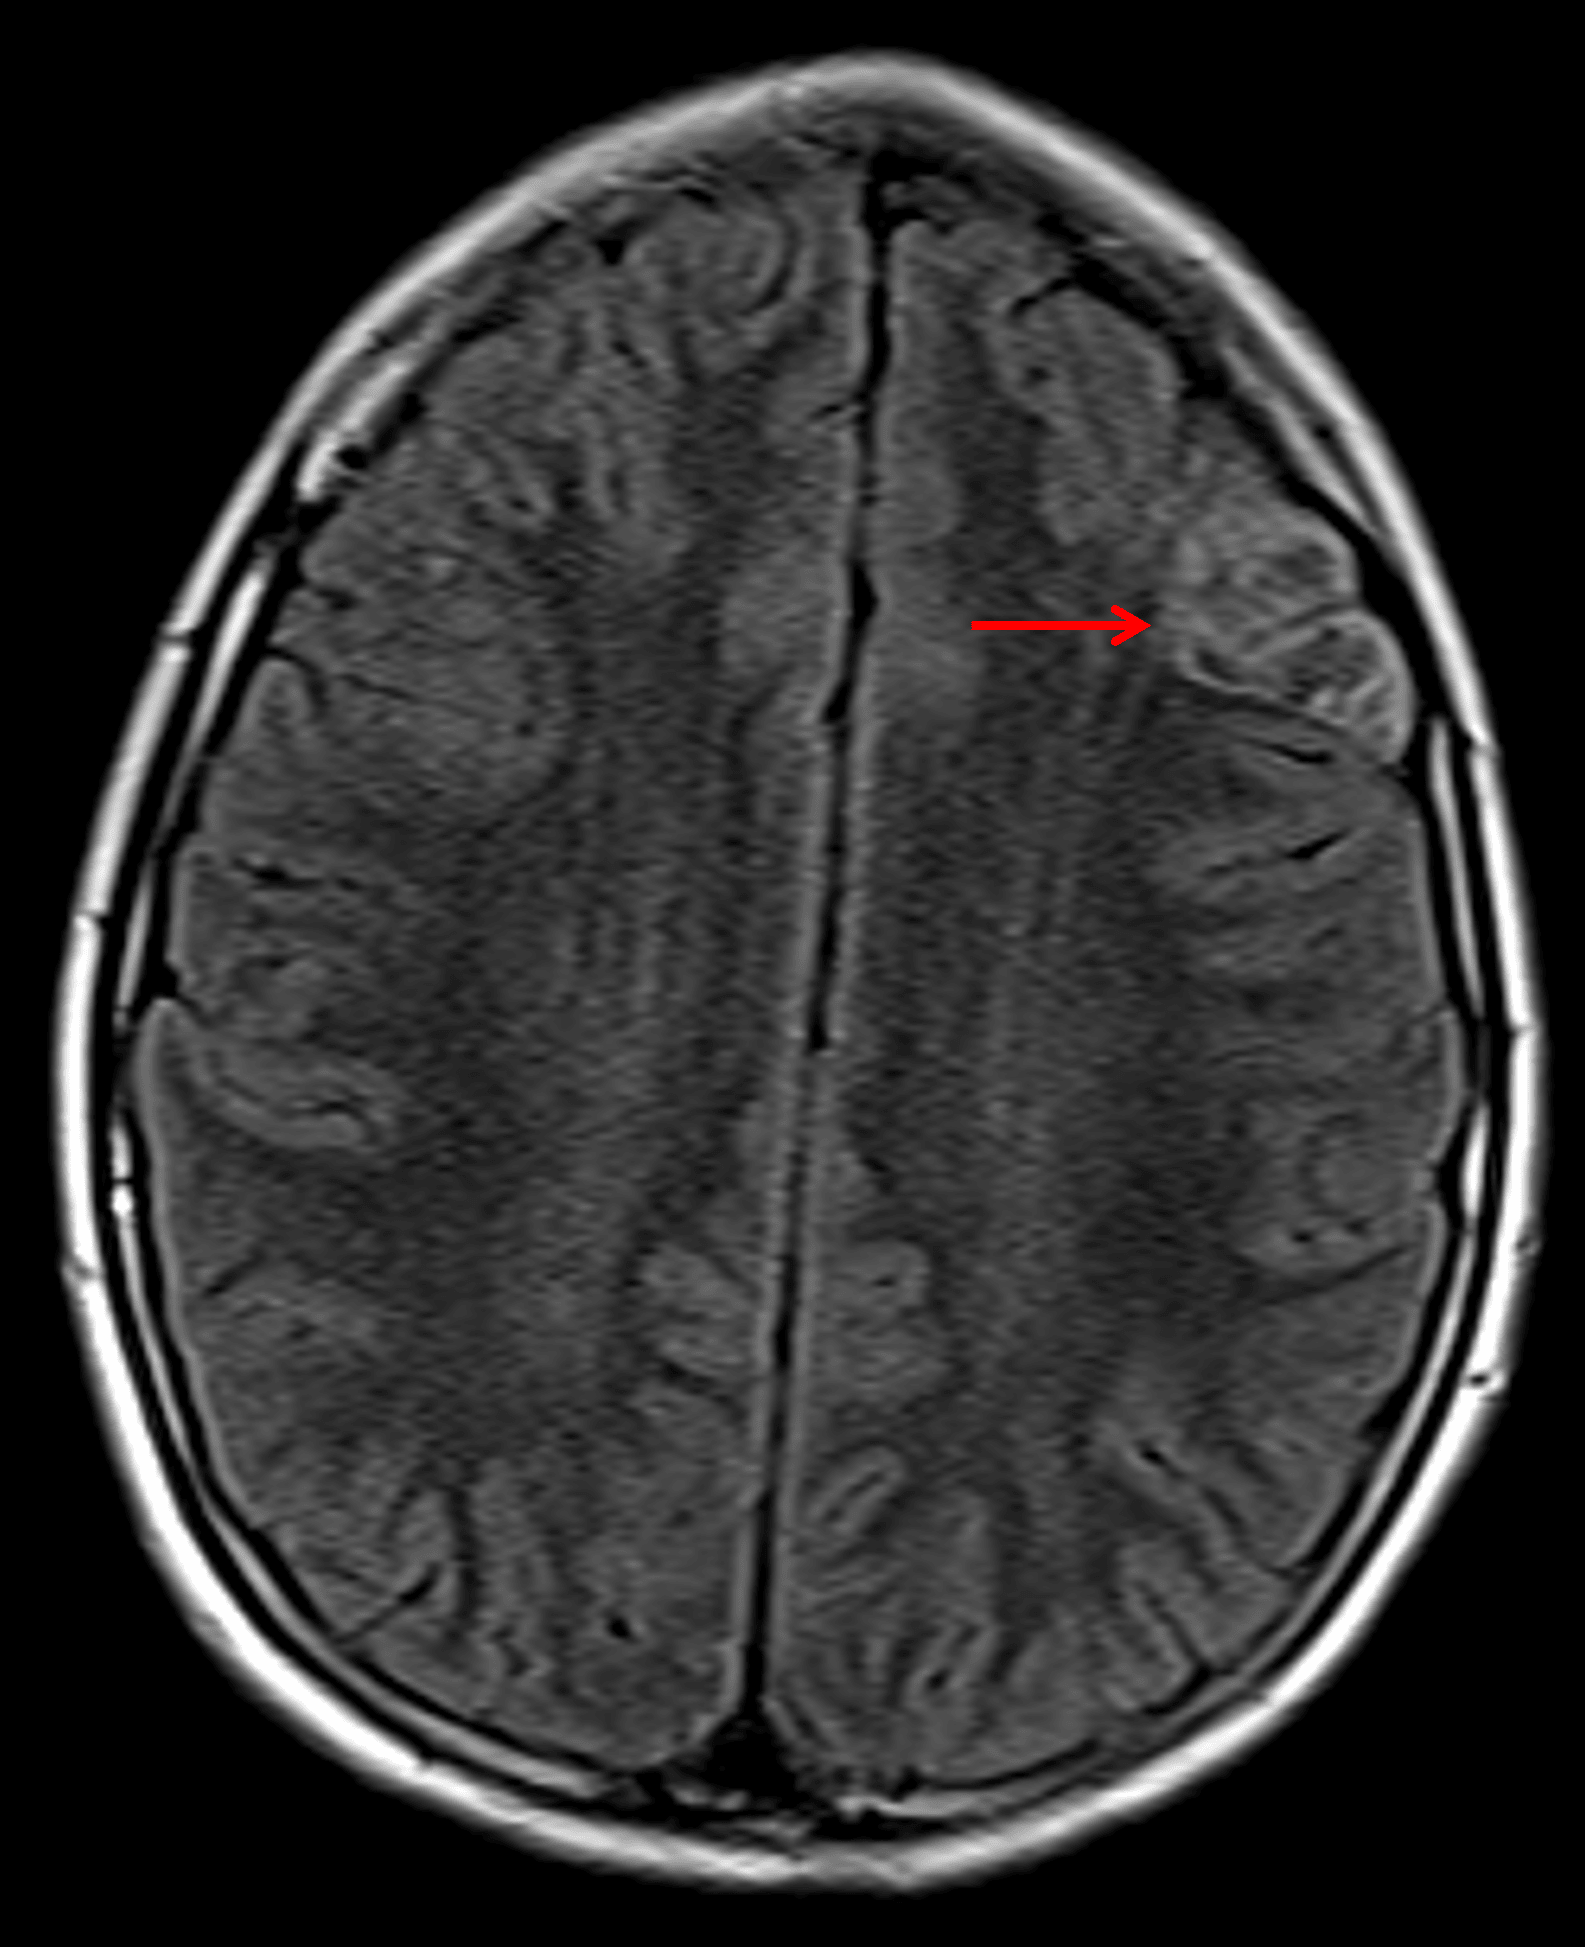

Note the heterogeneous internal FLAIR signal with a preserved hyperintense rim (red arrow).

Dysembryoplastic neuroepithelial tumor (DNET)